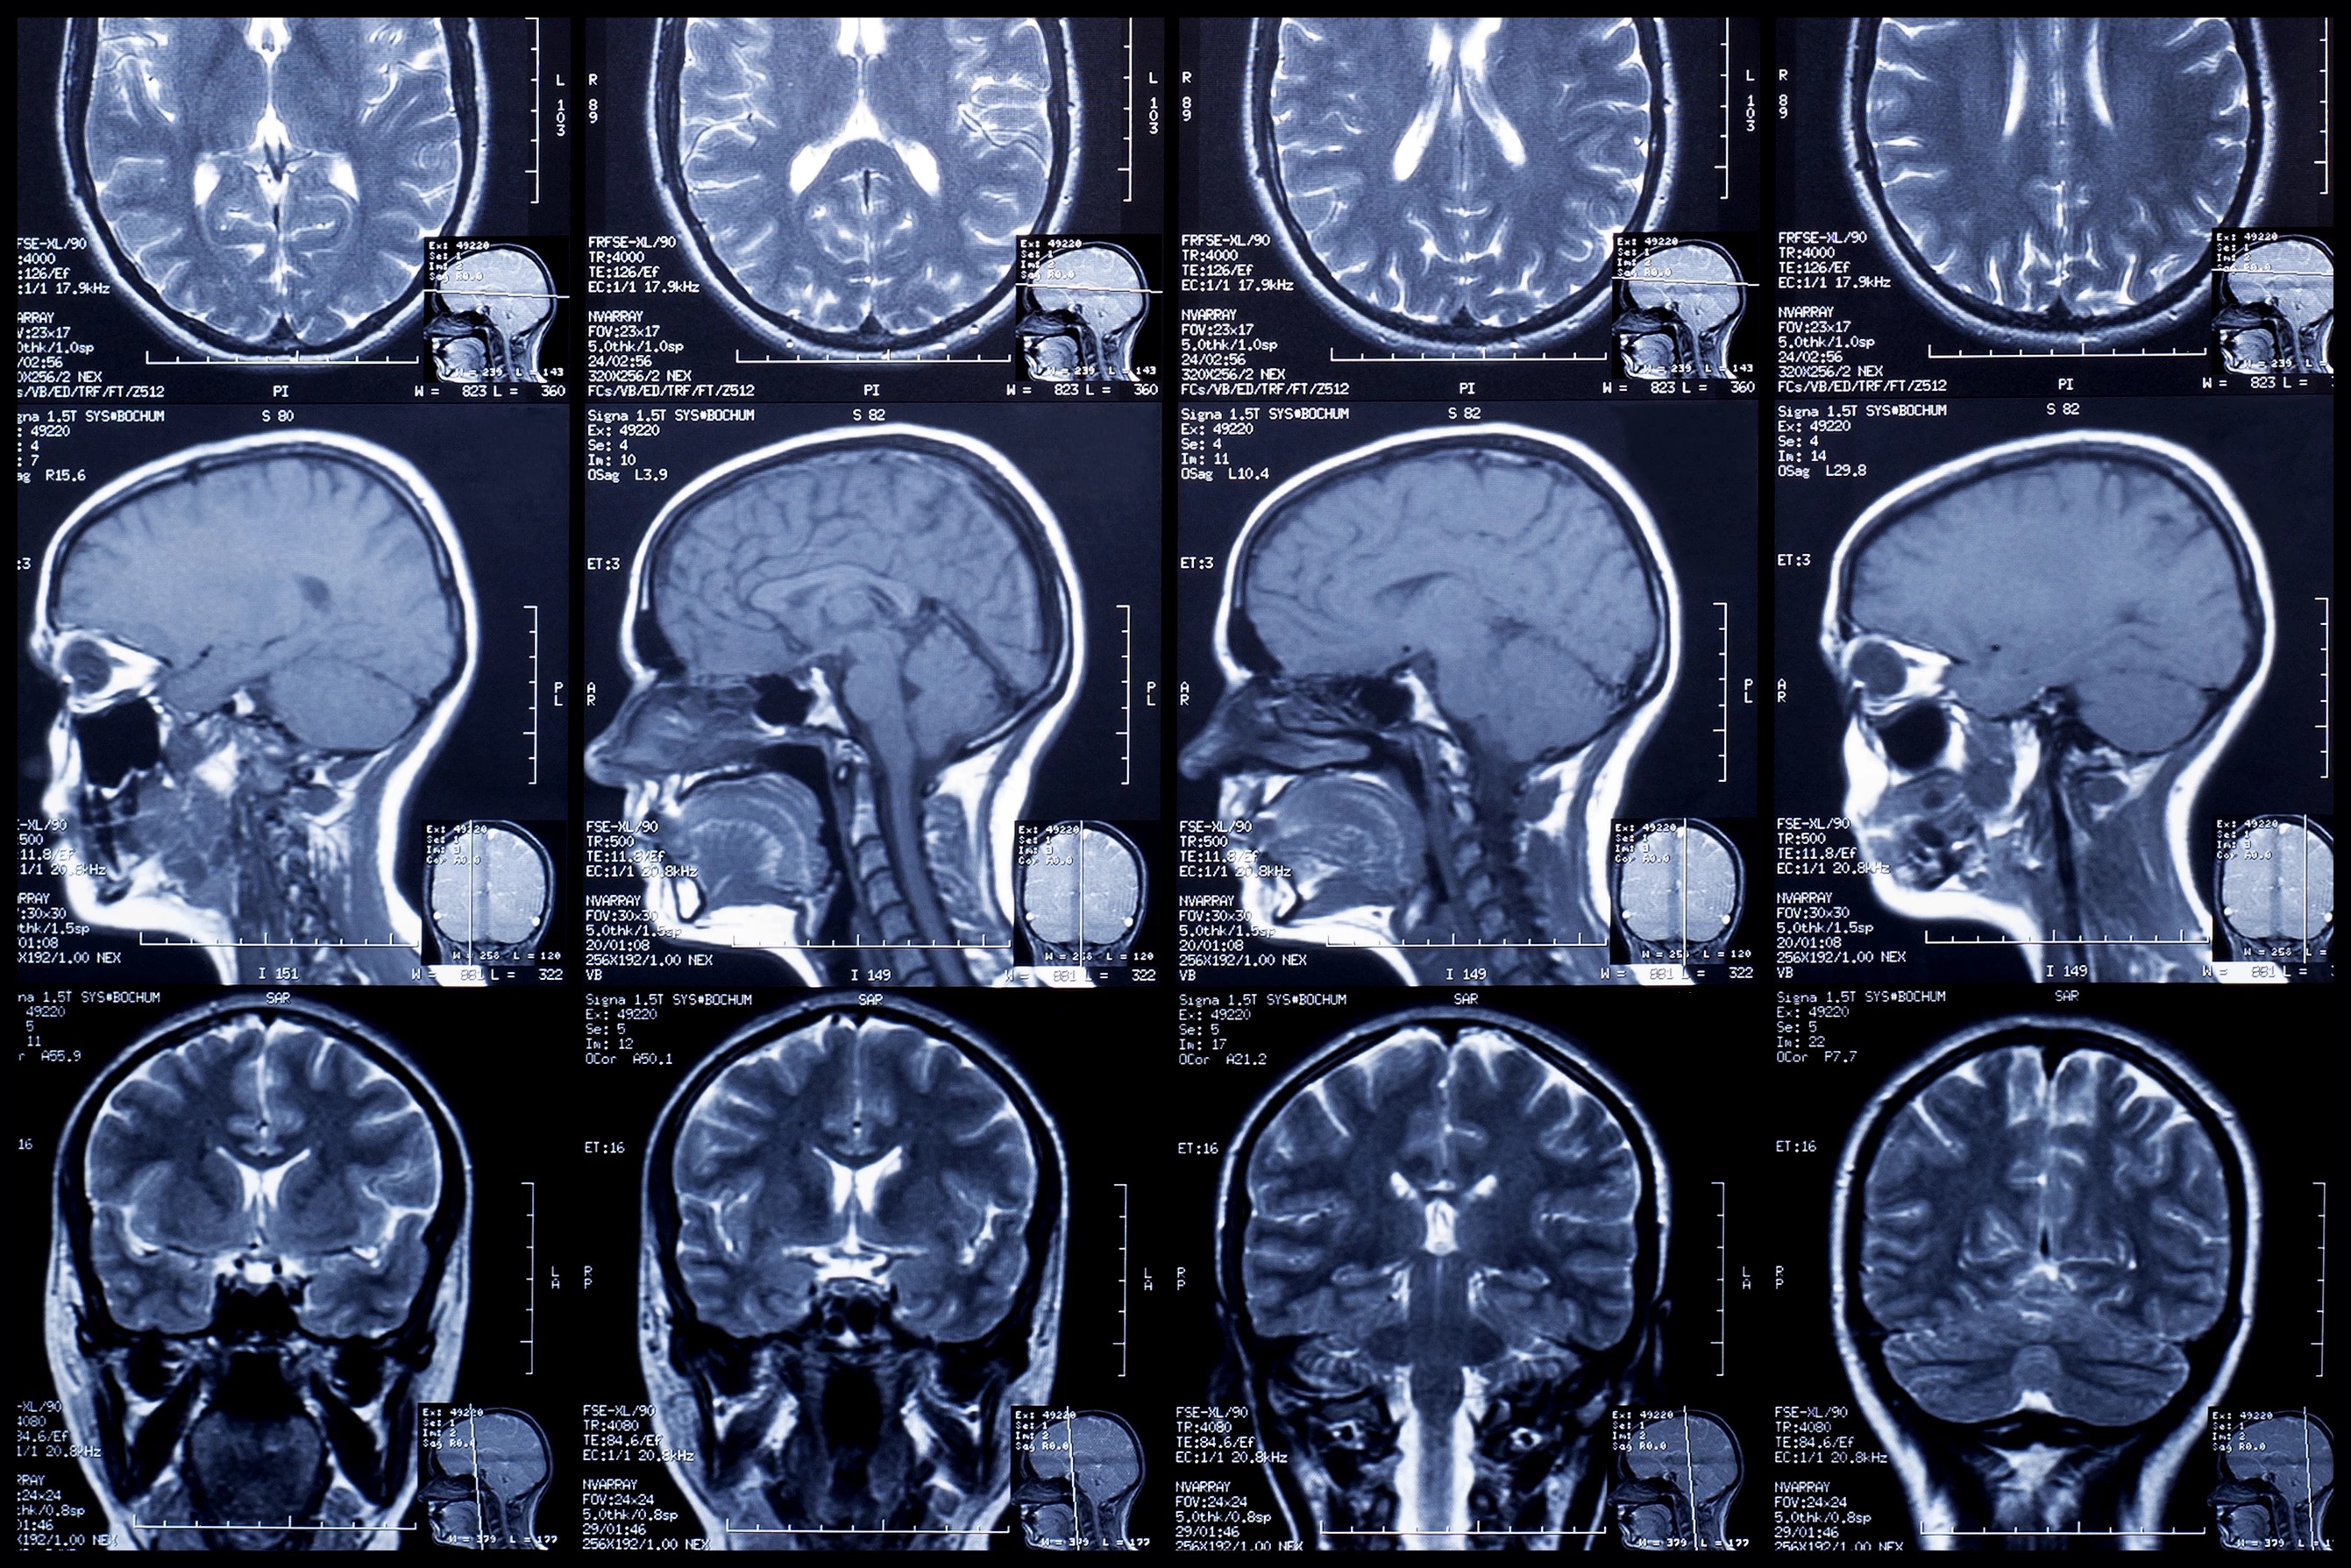

PVS is an oft-used term describe a patient who has lost all awareness of surroundings and self, displays no purposeful behaviors or intentional movements and has no capacity in higher brain functions such as decision making or problem solving.

A study published in BioMed Central Neurology indicates that doctors do not have the tools to diagnose the condition with certainty. A new tool, the JFK Coma Recovery Scale, is a barrage of more than 20 clinical tests that is designed to give doctors better insight into the cognitive abilities of their patients. Yet, over 40 percent of patients diagnosed PVS are not, in fact, in a persistent vegetative state, according to the Royal Hospital for Neurodisability in London.

It becomes a matter of what we really understand about the human brain, its resilience and the proper societal response to people with needs. We can choose to ignore the human condition, ignore the science and sentence innocent people to death. Likewise, we can choose to view medicine as an art—oftentimes brilliant and sometimes inconclusive.